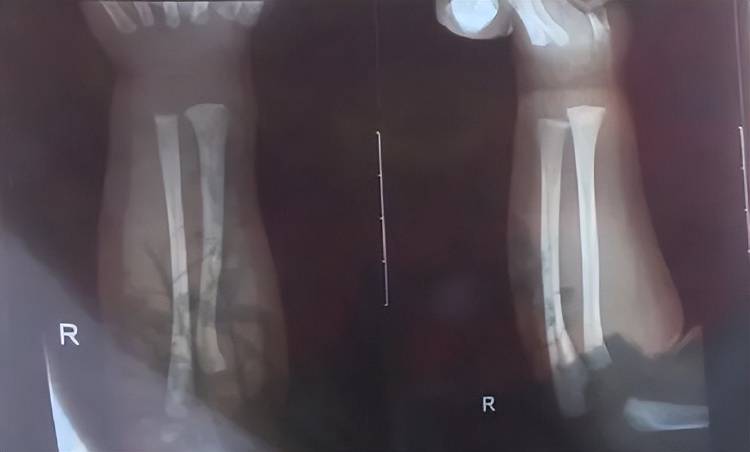

次日上午,孩子被带到附近医院检查,医生诊断发现他右手有两处骨折,第一处为右侧尺骨远端骨折,第二处为右侧桡骨远端骨折,随后医生给他做了石膏固定,“没想到,几天后孩子还被诊断出脑电图异常,医生建议复查btc交易平台。”

孩子被诊断发现两处骨折